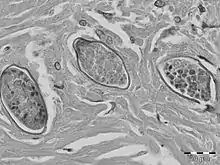

S. malayensis eggs have been found in liver granulomas, embedded within dense, fibrous tissue. The eggs of S. malayensis have a thin-walled, yellowish shell. The eggs contain miracidia and are approximately 50 μm long × 28 μm wide. The ova is not operculated and has no bipolar plugs and the thin covering was not striated.[6]